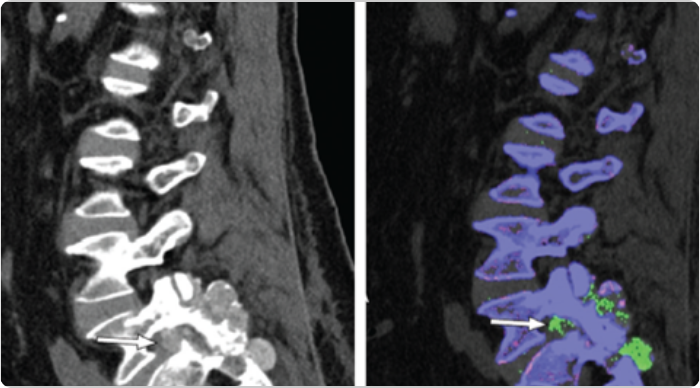

DECT scans of lumbar spine showing tophaceous deposits

Sagittal mixed 120-kVp equivalent images of lumbar spine obtained with dual-energy CT demonstrate an intermediate-attenuation mass in the L5-S1 facet joint with bony erosions and narrowing of the neural foramen (arrow, left). Dual-energy material labeling color map overlay shows monosodium urate (green) and bone (blue and pink). Note the monosodium urate crystals crowding the left neural foramen (arrow, right).3

Adapted from Gibney B, et al. Radiology. 2020;296:276.

KRYSTEXXA has not been studied to reverse damage to the spine or any of the body's organs.

CT, computed tomography.